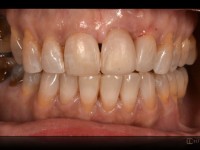

Caso de extrusión ortodóntica de un incisivo central superior para poder rehabilitar con implante dental.

La pieza presentaba movilidad, pérdida de soporte y el margen de encía en una posición muy elevada.

Mediante la extrusión con brackets, en la arcada superior se consiguió el desplazamiento de tejidos hasta una posición mas aceptable para así dar soporte al implante.

Después de 6 meses, se procedió a la rehabilitación de este incisivo con un implante osteointegrado y su propio diente como corona inmediata provisional